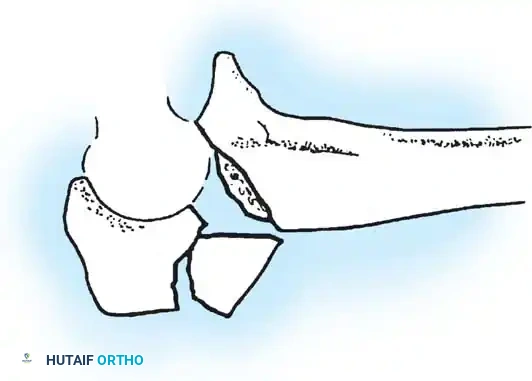

The primary goal of surgical intervention in the forearm and elbow is the exact restoration of anatomical alignment, axial length, and rotational stability. In the proximal ulna, the olecranon forms the greater sigmoid notch, articulating with the trochlea of the humerus. Any disruption here not only compromises the extensor mechanism but also threatens the intrinsic stability of the elbow joint.

FRACTURES OF THE OLECRANON

In adults, displaced fractures of the olecranon necessitate open reduction and internal fixation (ORIF). Because the olecranon is an intra-articular structure, reduction must be anatomically exact. Any residual irregularity or step-off of the articular surface inevitably leads to limited motion, delayed functional recovery, and early-onset post-traumatic osteoarthritis.

Olecranon fractures typically result from two distinct mechanisms:

1. Direct Trauma: A direct blow or fall onto the tip of the elbow. This mechanism frequently results in comminuted fracture patterns and significant articular cartilage damage.

2. Indirect Trauma: A fall onto a partially flexed elbow accompanied by a sudden, forceful contraction of the triceps muscle. This indirect force avulses the olecranon, typically resulting in a transverse or oblique fracture pattern with a clean articular break.